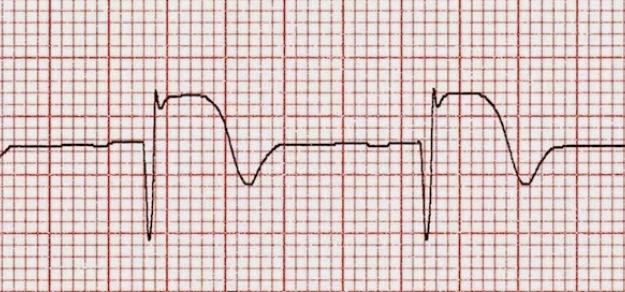

Uno de cada tres pacientes es derivado para reperfusión miocárdica, pero los derivados tienen menor probabilidad de recibir tratamiento de reperfusión y menor utilización de angioplastia primaria. Una mejor articulación de las redes podría mejorar el acceso y disminuir la morbimortalidad. Revista Argentina de Cardiología, 2017 Nº 2

- Cardiología